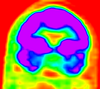

Intra-subject Brain PET-MRI with MRI orientation adjustment

fixed image/target | moving image |

- reference/fixed : baseline MRI:coronal T1w , 256 x 256 x 79, 0.86 x 0.86 x 2.5 mm

- moving: PET: axial, fluorodeoxyglucose, 128 x 128 x 35, 4.29 x 4.29 x 4.25 mm

- image content and resolution in PET is low